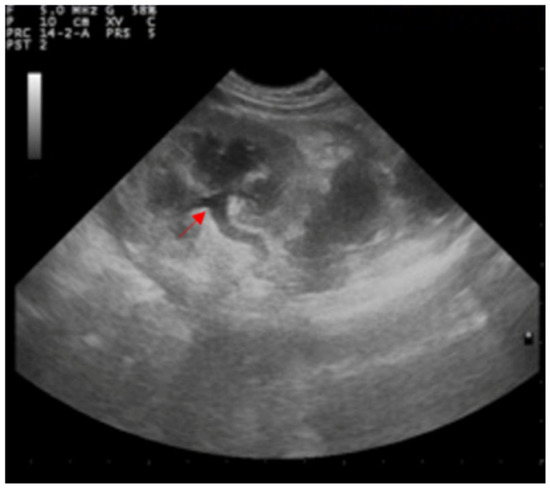

Both kidneys appeared to be enlarged with a dilated pelvis (4.5 mm), preserved echo structure, and intact renal capsule. Both ureters appeared to be dilated (5.6 mm), although the entire length of the left ureter was well-visible in contrast to the contralateral (Figure 3).

Figure 3.

Ultrasound examination of the left kidney showing the dilatation of the renal pelvis and ureter (red arrow).